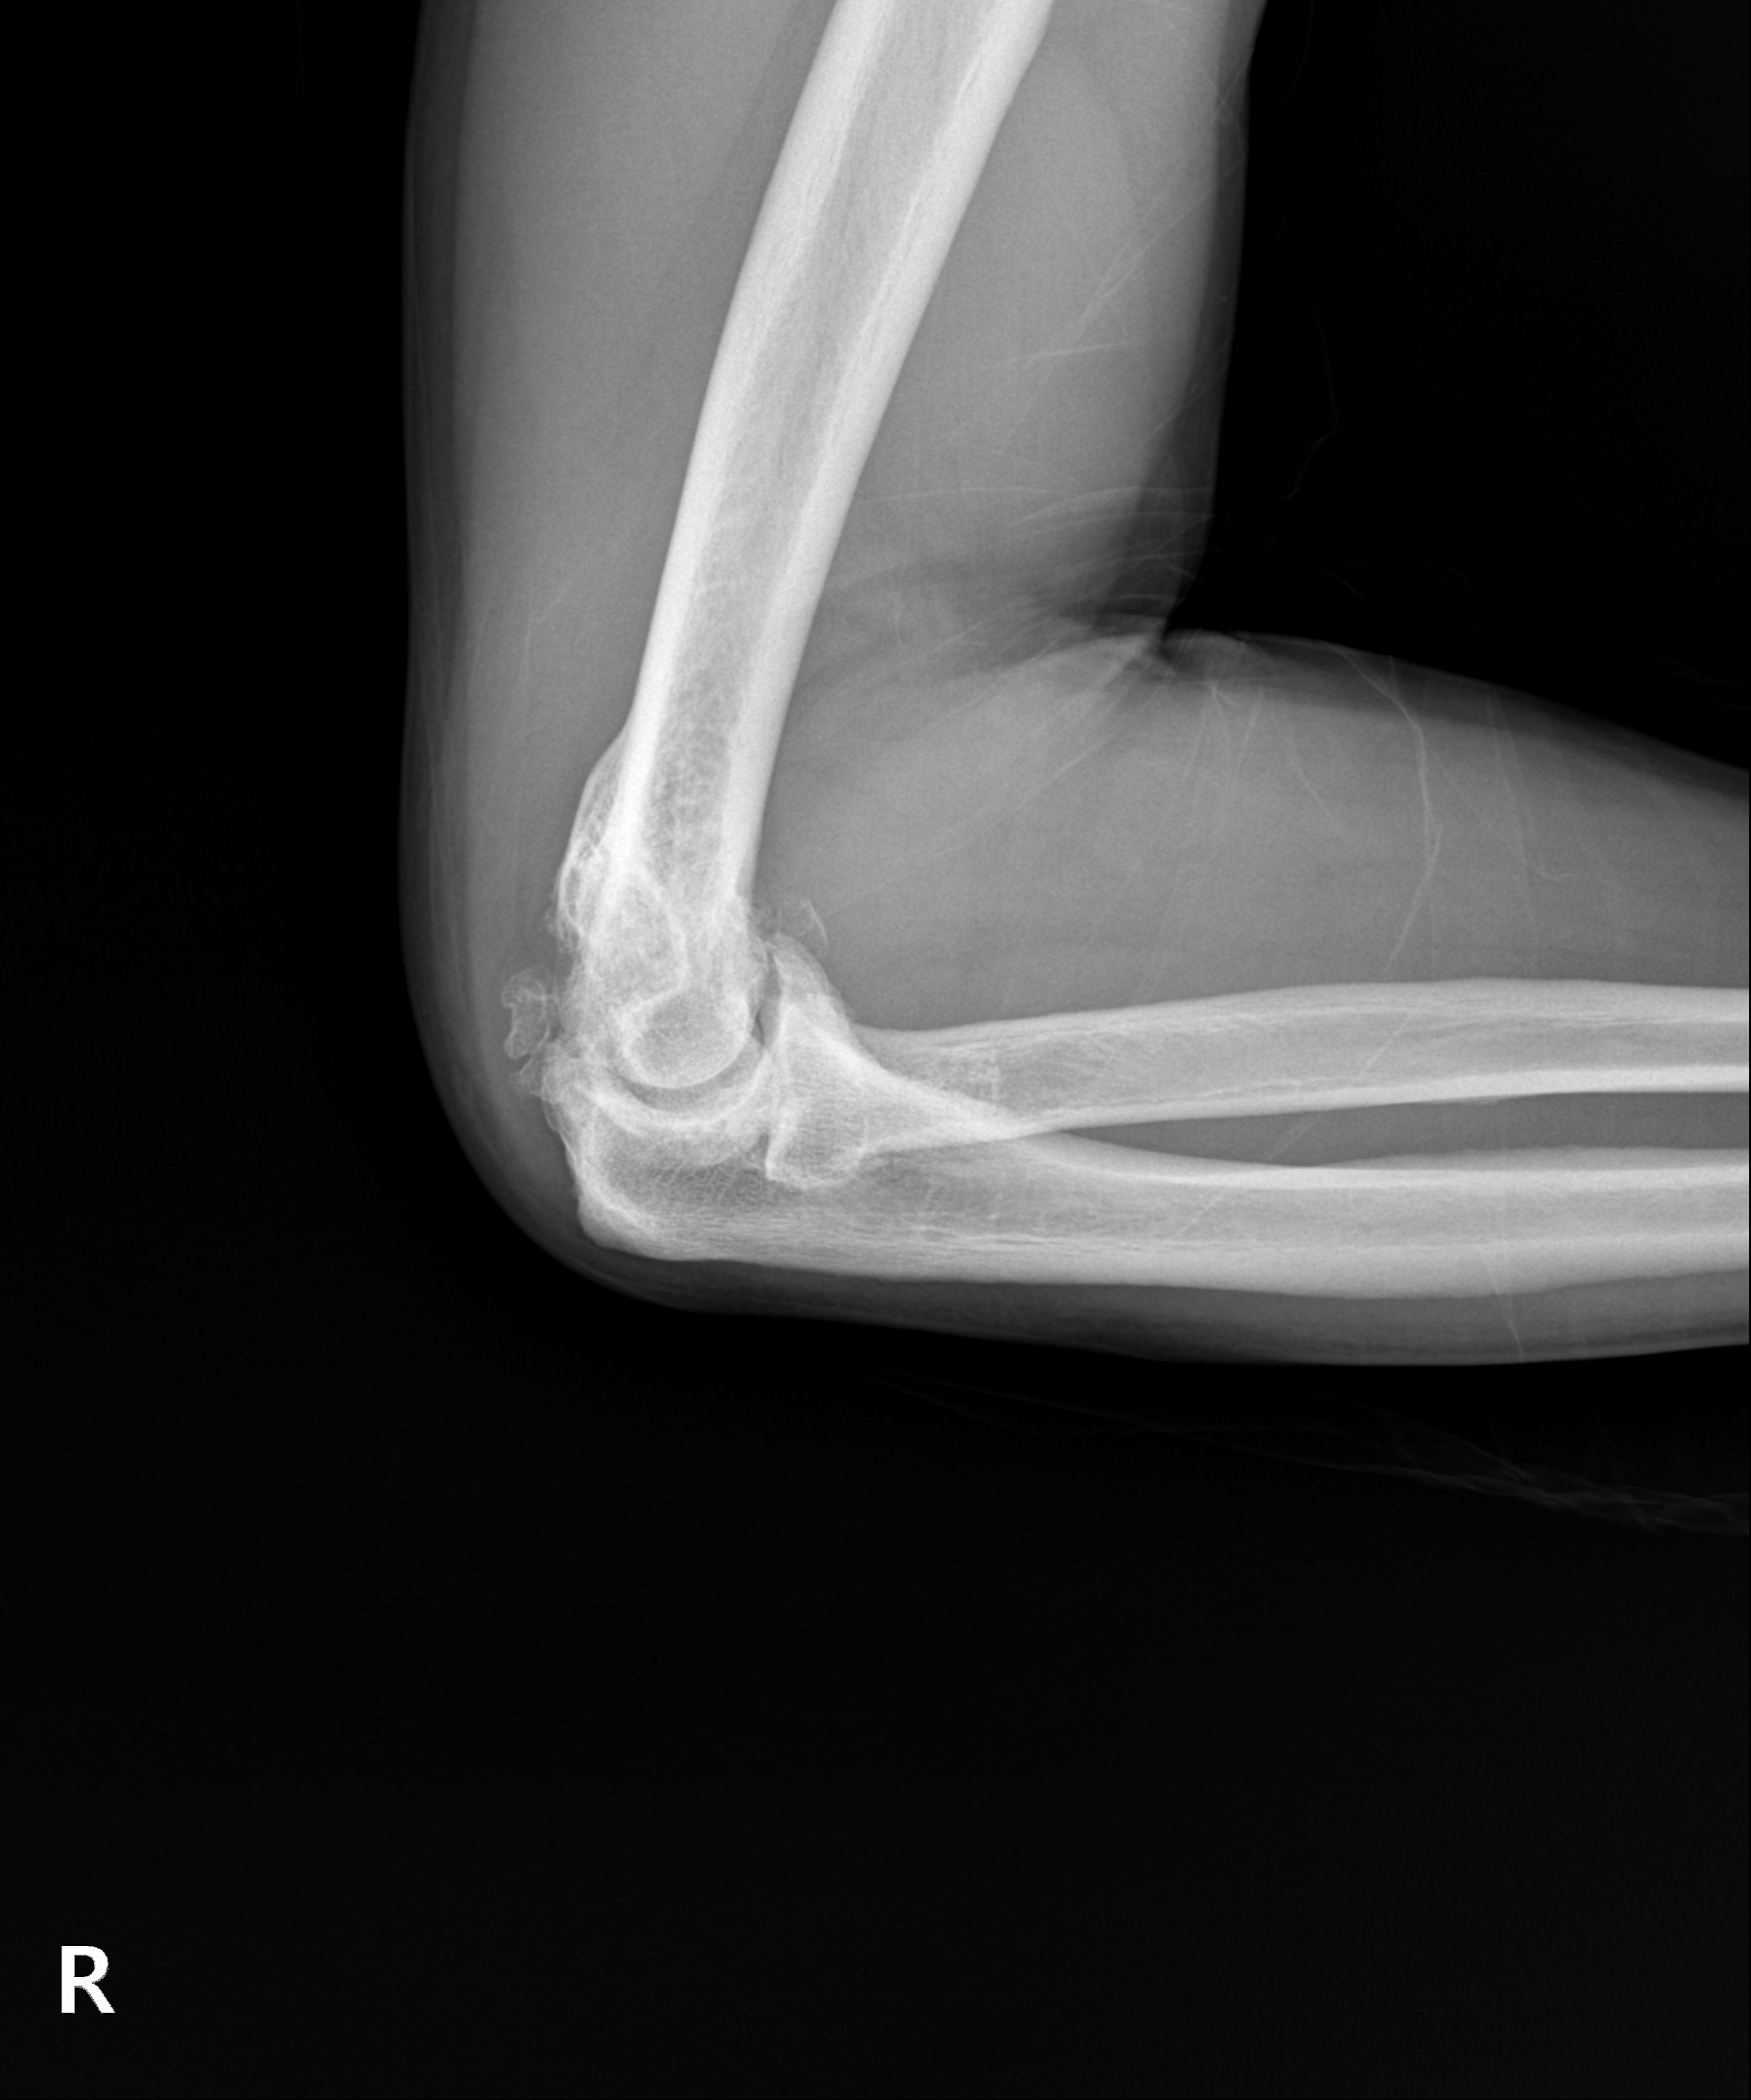

다른 부위 관절염처럼 팔꿈치 관절을 오랜 시간 과사용하여 관절이 손상되고 염증이 발생하는 질환입니다. 팔꿈치관절염은 시간이 지나며 점차 연골이 닳고 뼈가 자라나는 골극이 발생해 관절 가동 범위가 줄어들며 변형과 통증을 악화시킬 수 있습니다.

이미 관절 가동 범위에 제한이 온 팔꿈치 관절염은 뼈가 자라고

유리체 등이 관절면을 덮은 경우가 대부분으로 수술적 치료가 필요

관절내시경을 통해 자라난 뼈 조각과 관절 내 유리체를 제거하며

심한 경우 절개 수술이 함께 필요할 수 있습니다.